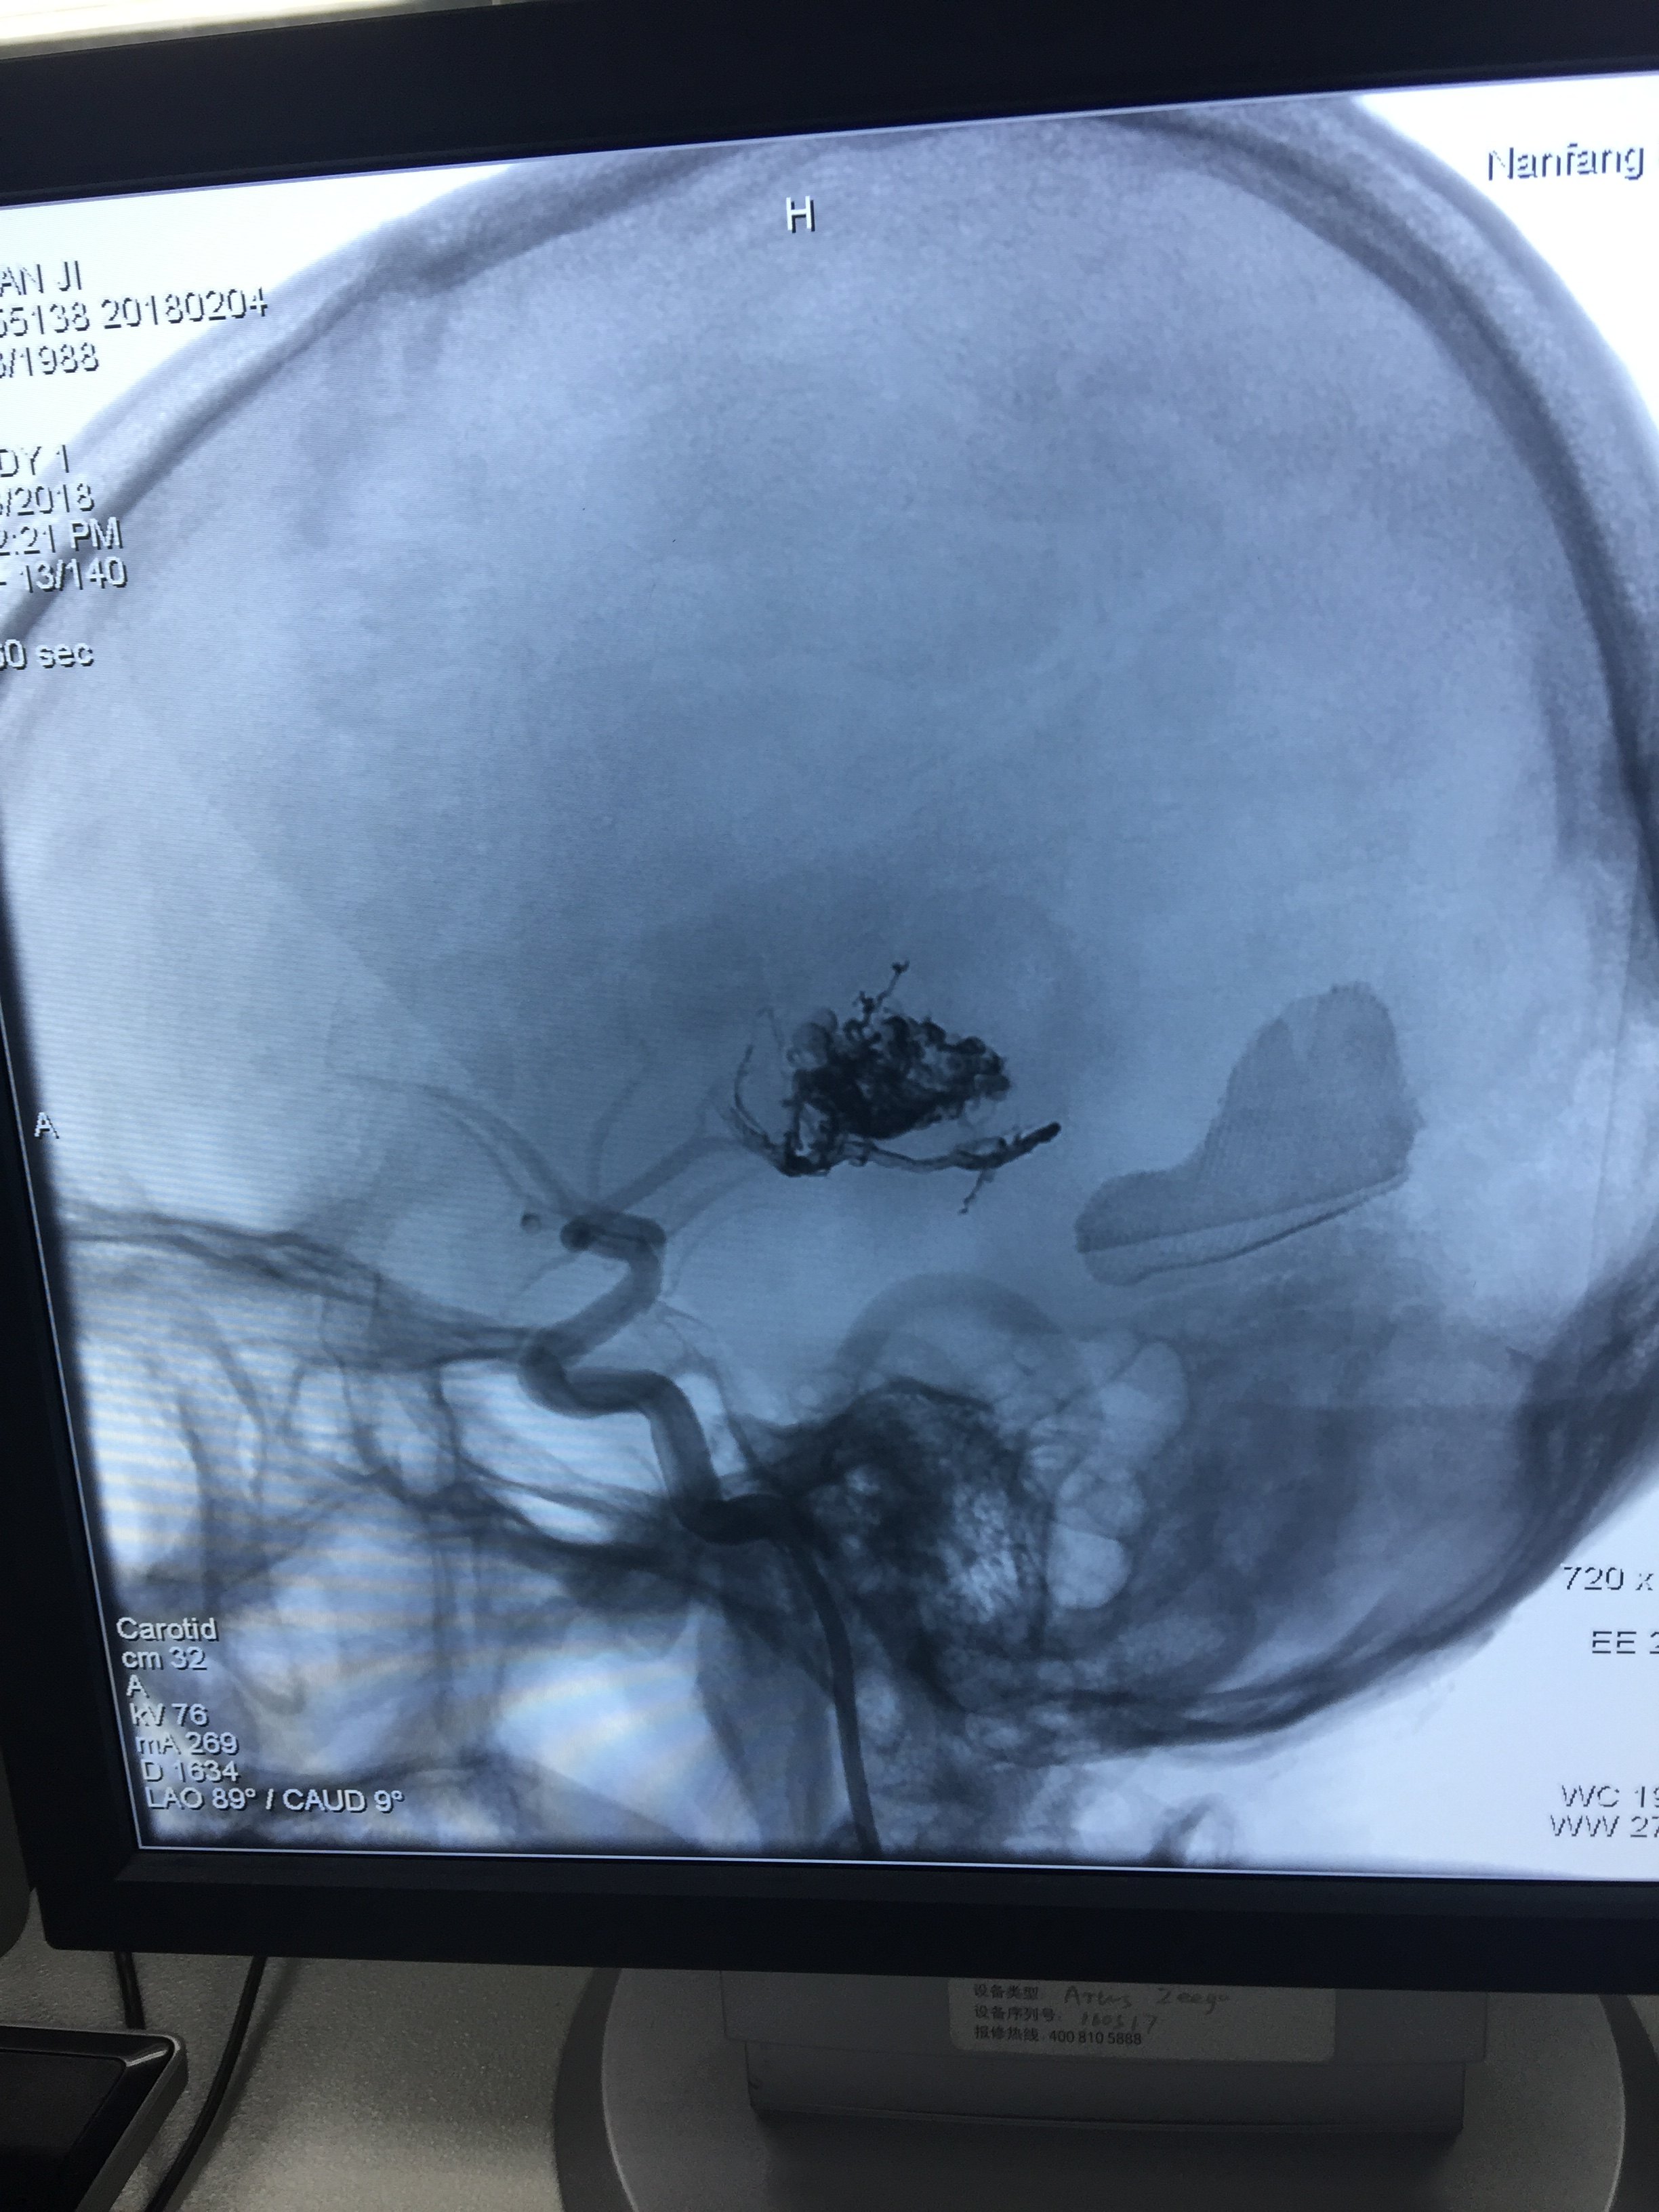

分享昨天做的一例脑动静脉畸形微创栓塞手术

术前造影:左侧颞叶脑动静脉畸形,此处因脑出血入院

微创栓塞后

栓塞剂的图片

术后患者无任何不适,效果好!